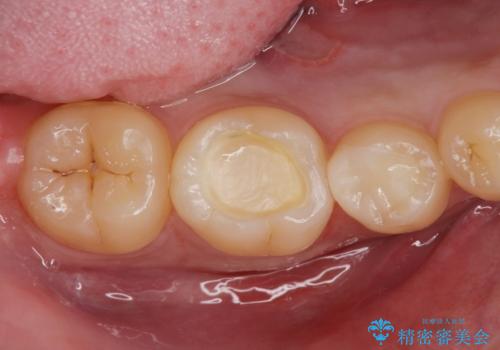

古い樹脂を除去してe-maxインレー

- 樹脂の材料での治療をセラミックに変えたいとの事で来院。

拡大鏡下で古い樹脂を除去し、虫歯がない事を確認してe-maxインレーで治療を行いました。

適合の良い詰め物が入りました。